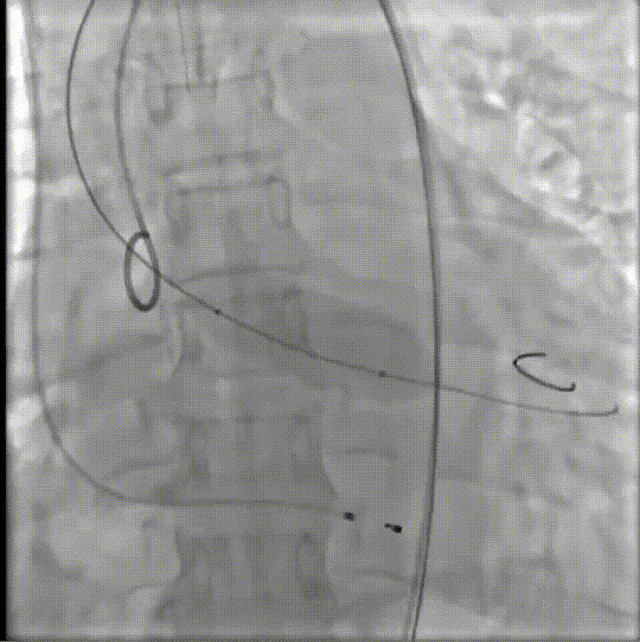

病例概览

患者病史 男性,74y, 因 “发现心脏瓣膜病 1 年,加重伴喘气半年” 入院。门诊检查显示主动脉瓣重度AS并伴轻-中度AR。患者基础疾病较多:胸腹主动脉多发穿透性溃疡、心功能III级等,手术指征明确,但风险极高。 术前CT LVOT- Annulus 倒梯形,对植入瓣膜有挤压位移风险,Annulus直径23.7mm,瓣叶增厚,钙化集中在无冠窦边缘。 左冠脉开口高度可,瓣叶不长、窦部空间较大,无冠脉风险;室间隔膜部较短,有一定PPI风险,心脏角度37.9°;心室较小,有一定循环崩溃风险,术前注意补液。 术前造影角度及入路:血管入路散在钙化、无迂曲;主动脉弓条件好、双侧股动脉直径大、右股穿刺点侧壁存在环形钙化 左右重合位:RAO 7° CAU 21° 右窦中心位:LAO2 1° CAU 1° 手术策略 20mm球囊预扩后植入AV26瓣膜,同时做好预防循环崩溃、传导阻滞的应急预案。 术中挑战 1)球囊预扩:20mm球囊预扩时无明显 “腰征”,但存在少量反流,提示瓣膜钙化与解剖结构对扩张的阻力不均 2)首次释放偏差:第一次定位释放时,瓣膜在 “开花” 过程中下滑约 3mm,工作位观察显示小弯侧瓣周漏较多(深度超过完全覆膜区),需二次调整。 3)二次精准定位:以猪尾导管为参照,将定位点调整至 “猪尾 - 2mm” 处,结合真实窦底深度(较深)重新释放,最终瓣膜位置稳定,瓣周漏显著减少。 术后即刻效果: 瓣膜形态良好,跨瓣压差从术前的 67mmHg 降至 6mmHg,且无明显瓣周漏,冠脉开口通畅; Commisural Alignment 术后即刻超声: Prostyle A®预装干瓣——助力临床最优化解决方案: √ 平衡的径向支撑力:特殊的解剖结构下位置形态良好,术后跨瓣压差大幅降低,血流动力学改善明显; √ 80%可回收设计:支持术中二次调整释放位置,保证精准释放; √ 平衡的收腰设计&Commissural Alignment设计: 为患者后期冠脉PCI保留了生命通道;